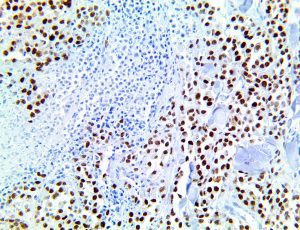

It is the ICU physician who is most likely to witness one of the deadliest manifestations of the abnormal immunological response, the cytokine storm syndrome (CSS). This response is also referred to by some as the cytokine release syndrome (CRS). CSS is characterized by continuous activation and expansion of macrophage and lymphocyte populations, which secrete large amounts of cytokines, causing the cytokine storm. This massive cytokine release is akin to hemophagocytic lymphohistiocytosis (HLH) disease, a syndrome characterized by initial unchecked and persistent activation of cytotoxic T lymphocytes and NK cells.

Clinical and laboratory manifestations of HLH include fever, enlarged liver and/or spleen, neurologic dysfunction, coagulopathy, liver dysfunction, cytopenias (i.e., low levels of erythrocytes, leukocytes, and/or platelets), hypertriglyceridemia, hyperferritinemia, hemophagocytosis, and eventually diminished NK cell activity as the immune system becomes progressively paralyzed. HLH can be familial (primary HLH) or secondary to another disease process (sHLH), such as rheumatic disease, in which it is referred to as macrophage activation syndrome (MAS, characterized by elevated ferritin).